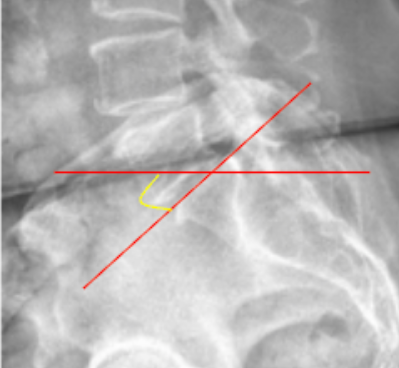

Mcnab's Line